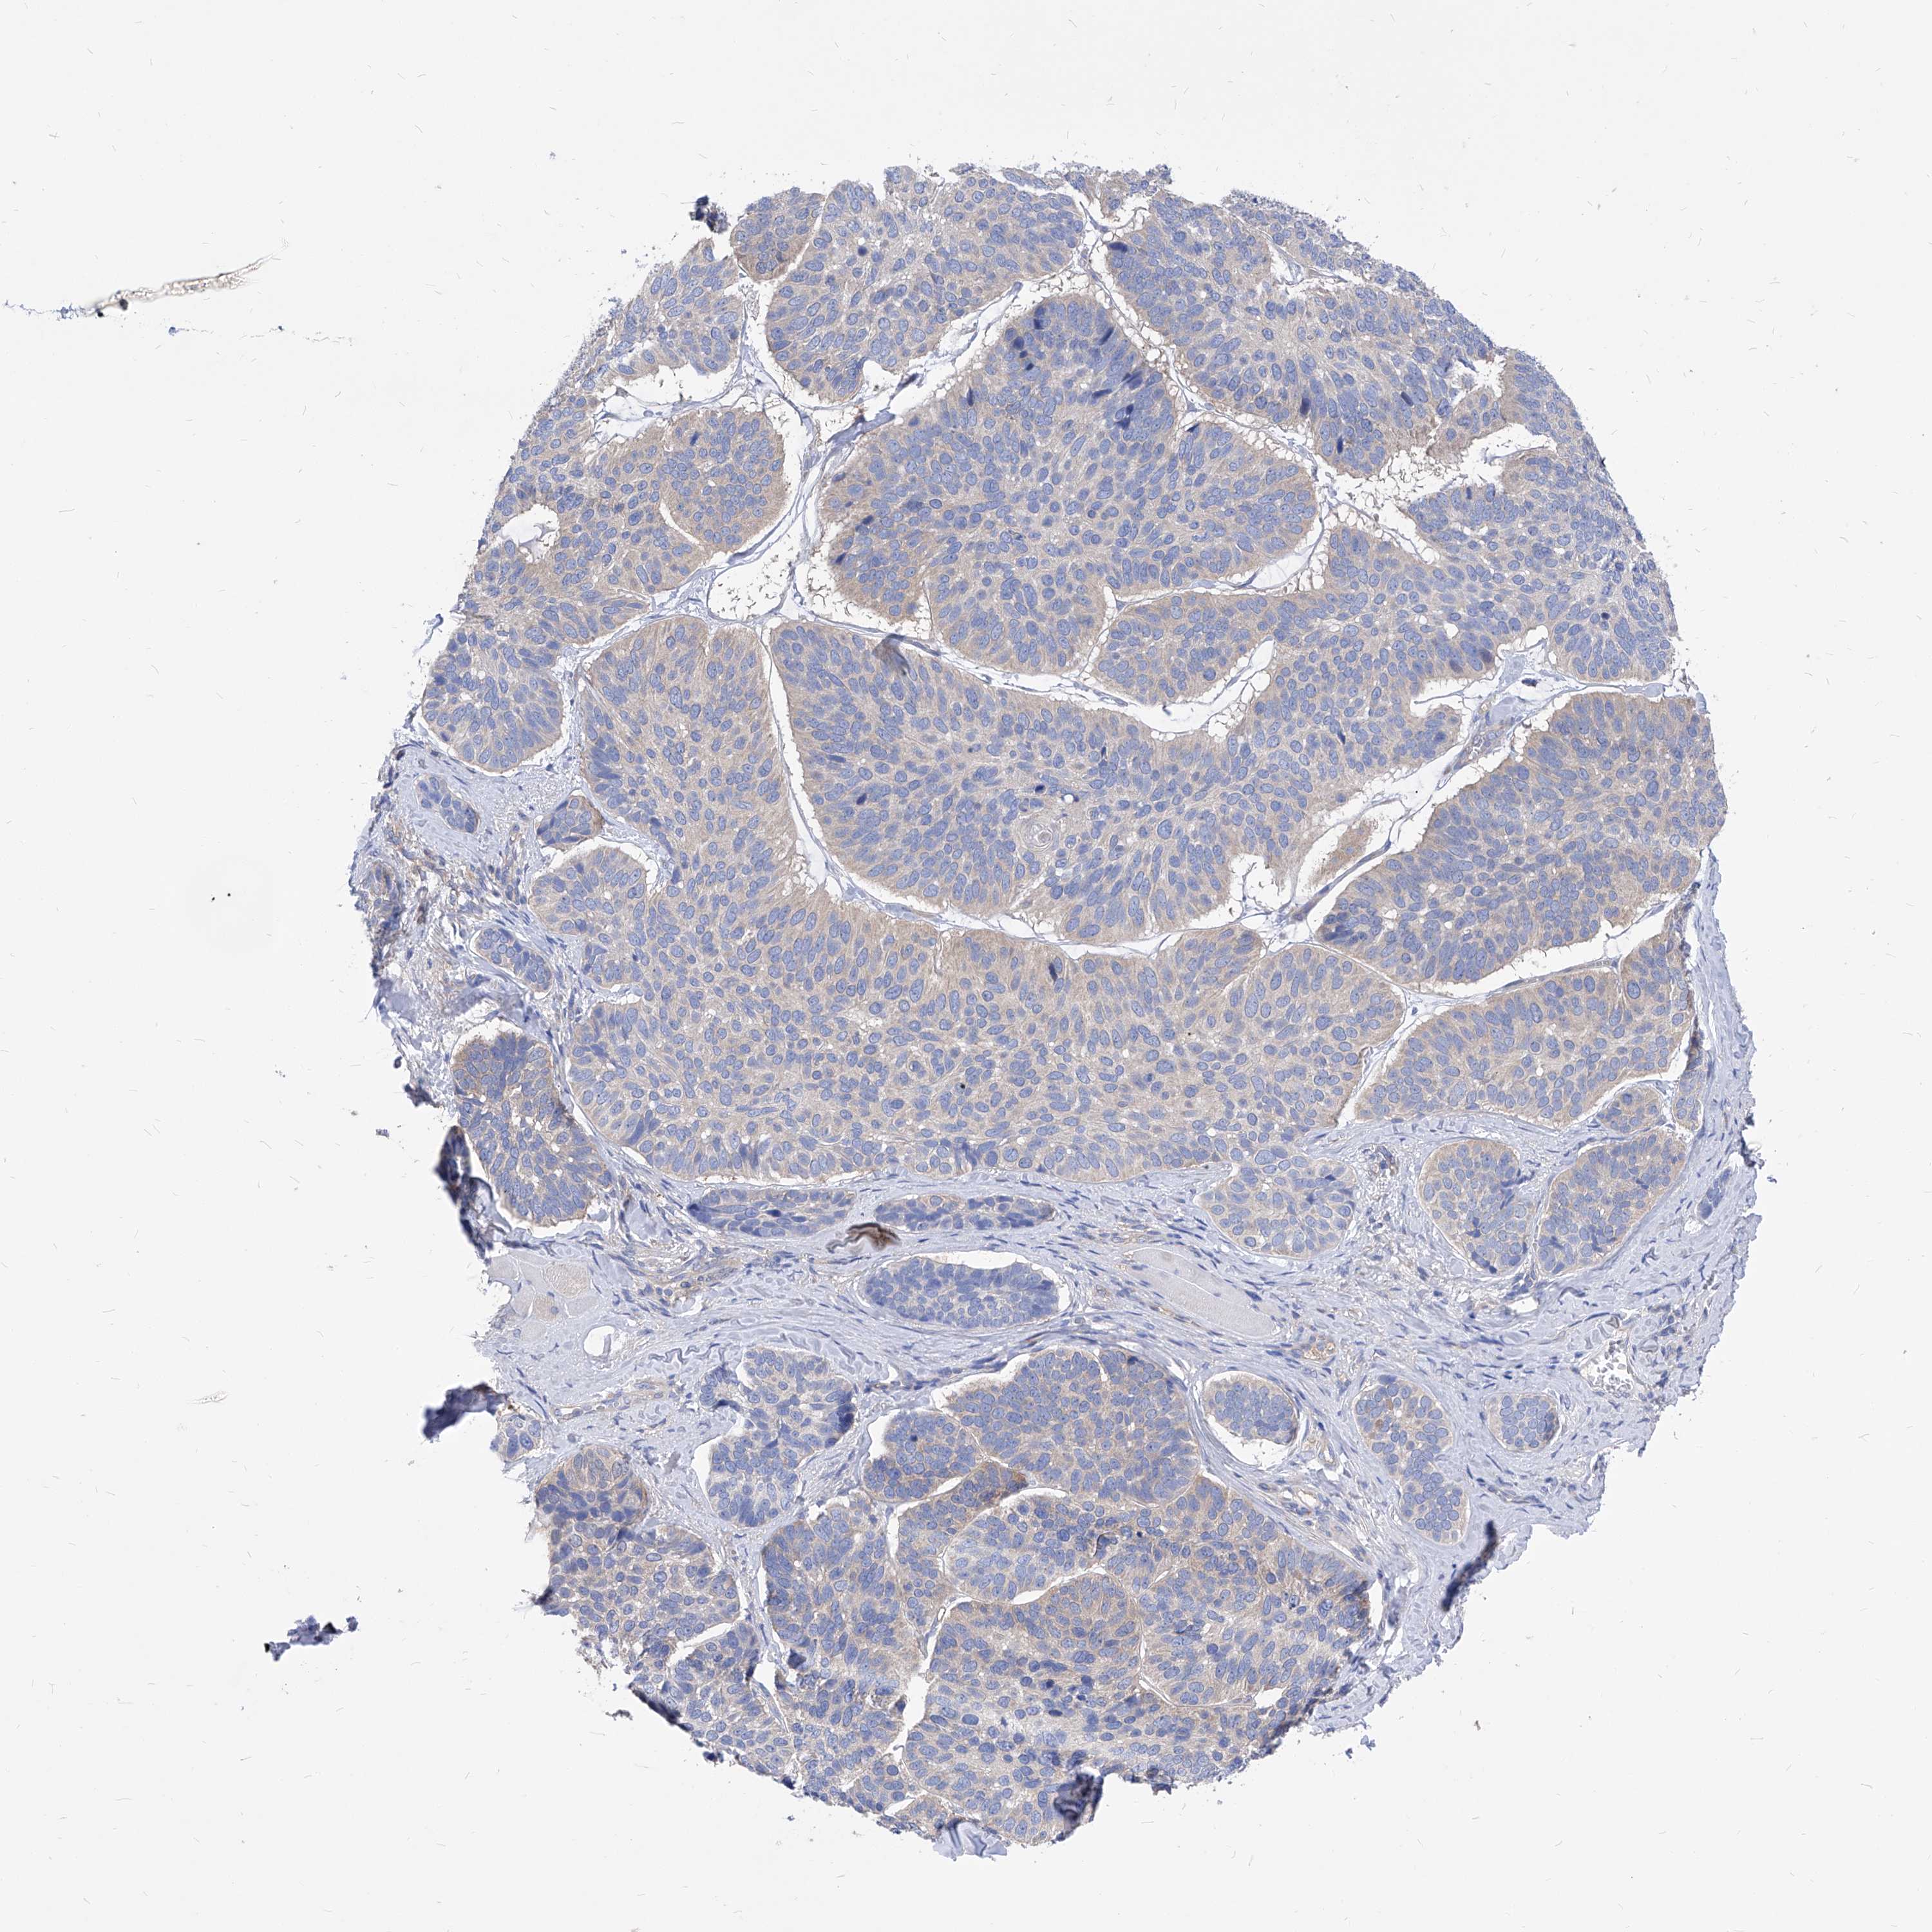

CANCER SKIN CANCER Show tissue menu

Basal cell and squamous cell cancer

SKIN CANCER - Protein expressioni

A mouse-over function shows sample information and annotation data. Click on an image to view it in a full screen mode. Samples can be filtered based on level of antibody staining by selecting one or several of the following categories: high, medium, low and not detected. The assay and annotation is described here.

Antibody stainingi

Antibody staining in the annotated cell types in the current human tissue is reported as not detected, low, medium, or high, based on conventional immunohistochemistry profiling in selected tissues. This score is based on the combination of the staining intensity and fraction of stained cells.

Each image is clickable and will lead to virtual microscopy that enables deeper exploration of all samples and also displays staining intensity scores, fraction scores and subcellular localization as well as patient and tissue information for each sample.

Basal cell carcinoma